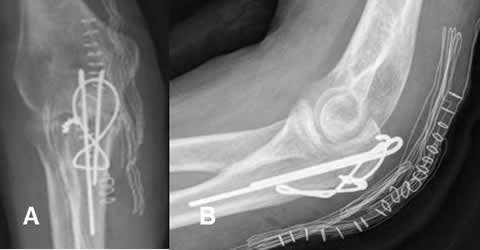

Fig 103. Técnica combinada.

A: Rx AP y B: Rx lateral. Fractura del olécranon, estabilizada con agujas y alambres.